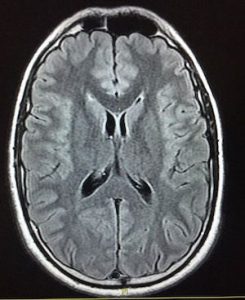

C’est vrai que c’est pas évident du tout mais en général les os beaucoup plus blanc au scanner que sur IRM

- 4A3BC8B6-58C1-4ED4-8F8F-FAFD1E9C5D33.jpeg (16.57 Kio) Vu 238 fois

= IRM